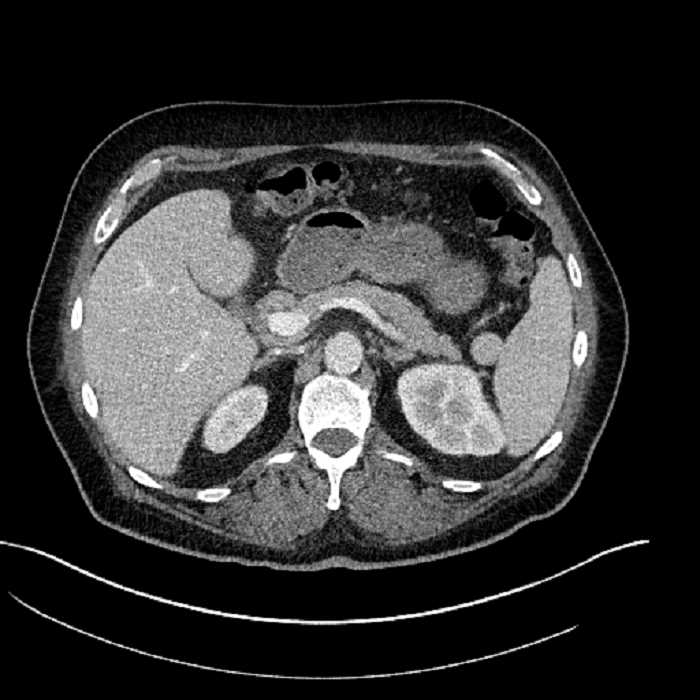

Age: 63

Sex: Male

Indication: Abdominal pain

• Mild mural thickening of a segment of the sigmoid colon with adjacent fat stranding and a 1.5 cm fluid and gas collection along the tip of an inflamed diverticulum

• Loss of the normal fat plane between this collection and adjacent loops of small bowel, which demonstrate mural thickening

• No bowel obstruction

Acute sigmoid diverticulitis complicated by a small contained perforation and a large abscess in the right hepatic lobe. Additional small subcapsular abscesses along the anterior margin of the left hepatic lobe.

Additionally, loss of the normal fat plane between the peridiverticular collection and adjacent thickened loops of small bowel raises the potential for an enterocolonic fistula.

Hepatic abscess showing the double target sign with low density internally surrounded by a thin inner enhancing rim (red arrow) and ill-defined outer low density rim (yellow arrow). Blue arrow indicates an internal septation. Red arrows: additional smaller subcapsular abscesses. Red arrow: focal contained perforation associated with diverticulitis.